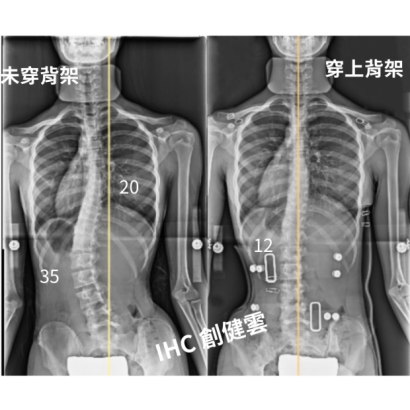

33歲脊椎側彎成年女性,胸彎20度,腰彎25度

33歲脊椎側彎成年女性,胸彎20度,腰彎25度 穿上背架後立即矯正效果優異